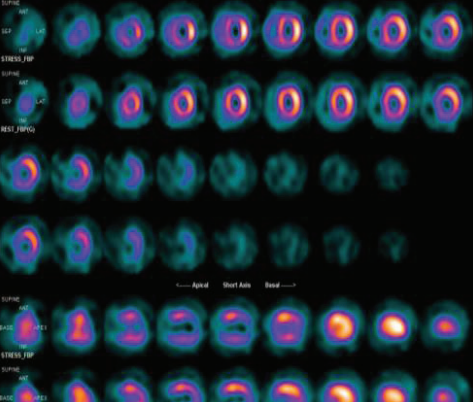

• Na doença arterial coronariana estabelecida – Após o diagnóstico, o ecocardiograma avalia a função ventricular e é útil no seguimento clínico para detectar complicações. Os testes de estresse físico ou farmacológico com imagem ecocardiográfica podem identificar isquemia.